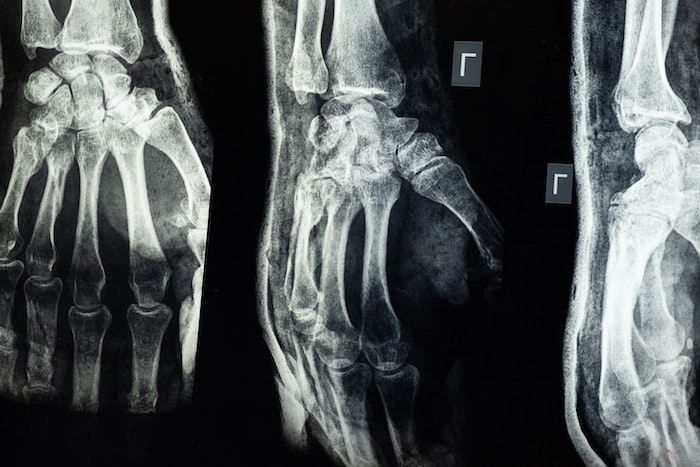

2. Fraturas

As fraturas nos ossos ocorrem após um forte impacto. E uma das principais razões para que isso aconteça é após um forte impacto como uma queda. Uma fratura é um trauma, só que mais grave porque pode trincar ou quebrar o osso.

E esse problema ainda pode ser sentido pelas pessoas dias depois de ocorrer, o que torna ainda mais grave o quadro.

O teste mais comum e prático para determinar se existe mesmo uma fratura óssea é o raio-X. Após o procedimento, o resultado é rápido e dá ao médico a certeza de que há uma lesão óssea.